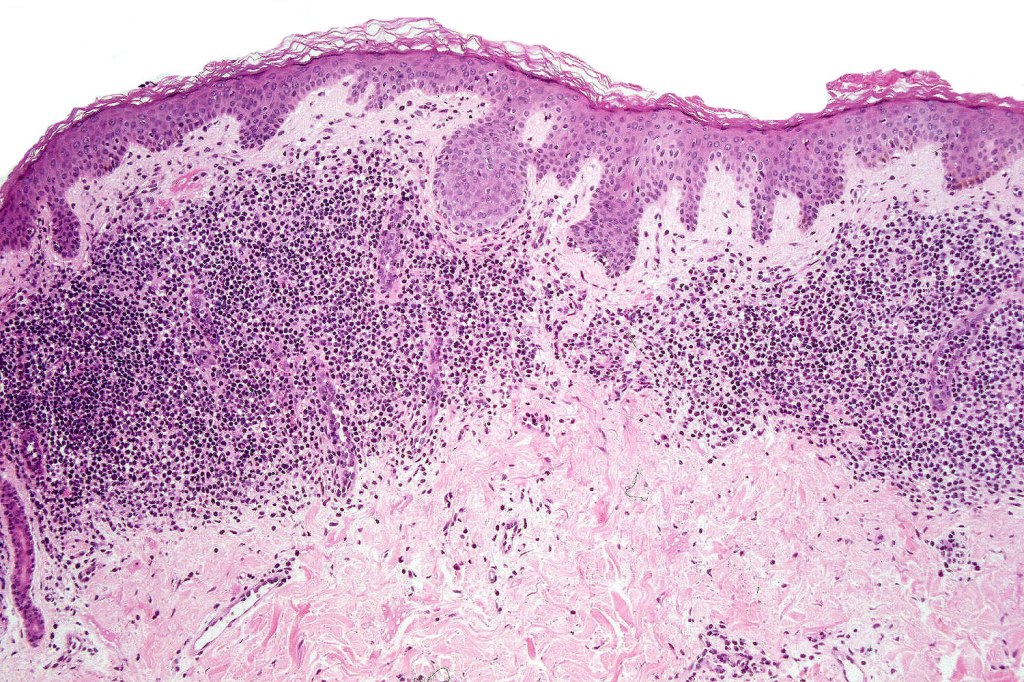

Histological features

•Variable histological features ranging from a non-specific superficial perivascular or band-like dermal infiltrate with minimal or no epidermotropism through to mycosis fungoides-like histology; can mimic atopic dermatitis